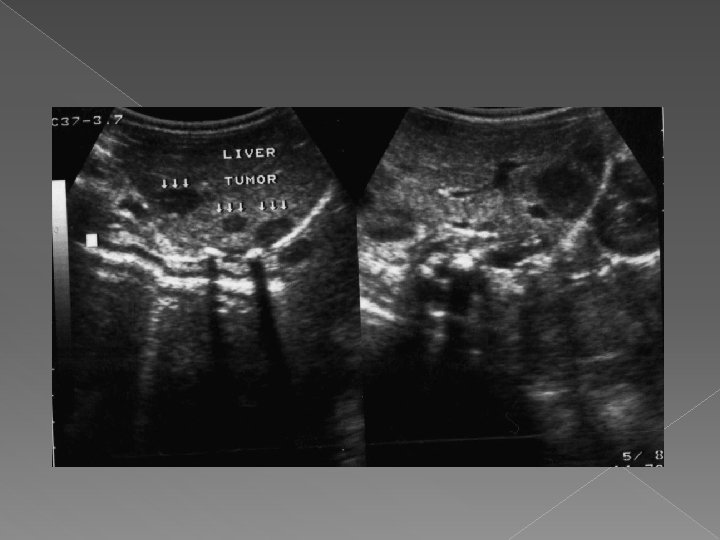

Ultrasonografia : -uzuala, rapida, accesibila, informativa; -ideala pentru leziuni focale cu continut fluid; -tumorile solide sint mai greu de diferentiat. Scintigrafia: -rezultate bune in indentificarea leziunilor focale; -are valoare in aprecierea volumului si configuratia hepatica; -slaba specificitate.

Metastaze hepatice